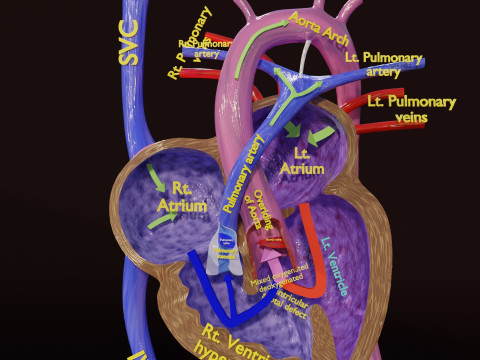

The model meshes include adult circulation versus circulation in Tetralogy of Fallot (TAF), arrow labels and text labels. The blood flow in a patient with Tetralogy of Fallot is outlined in this model. To contrast it to normal blood circulation a separate model of normal circulation is included. The Tetralogy of Fallot (OVER RIDING OF AORTA, PUL STENOSIS, VENTRICULAR SEPTAL DEFECT, RIGHT VENTRICULAR HYPERTROPHY), fossa, ligament teres , venosus, and arteriosus are duly depicted with proper labelling and blood flow directional arrows. Excellent model for teaching, demonstration and knowlegde of human body. The models include both procedural and image textures blend files separately. The texture file include diffuse, roughness and normal png and jpeg based on non overlapping UV maps.